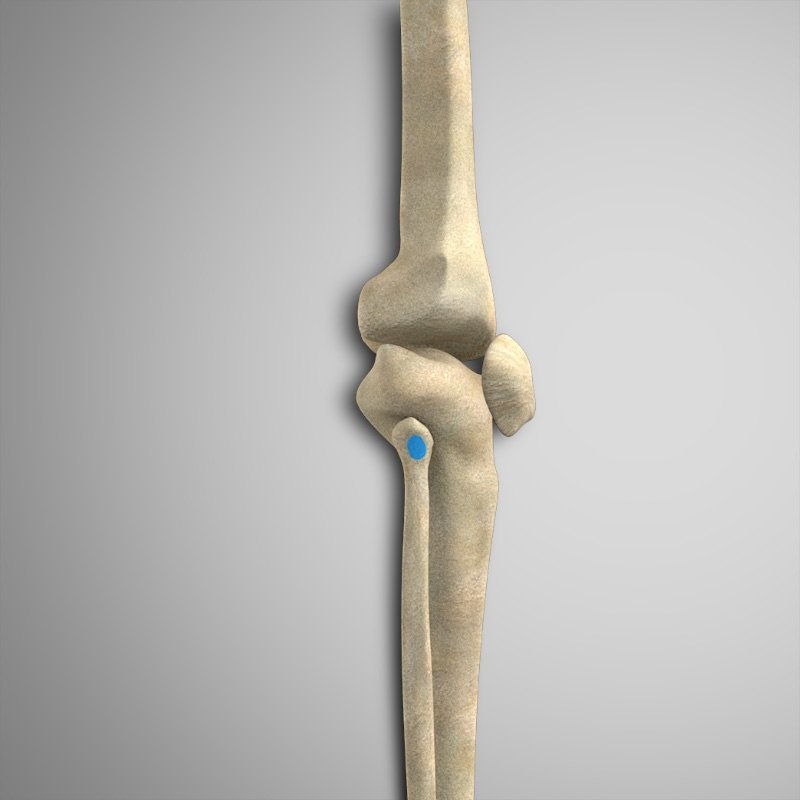

- Bíceps femoral (ambas cabezas) – Cabeza del peroné

- Semimembranoso – Cóndilo tibial medial posterior

- Semitendinoso – Tendón anserino.